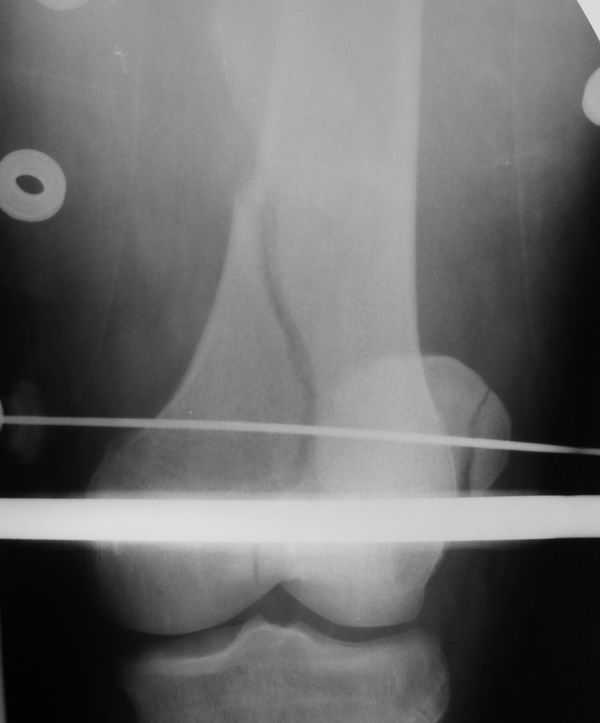

Лечился в ЦРБ. К нам поступил вчера. Имеется оскольчатый перелом диафиза левого бедра, перелом медиального мыщелка, краевой перелом надколенника. У нас, кроме того, выявили перелом шейки бедра. Перелом закрытый, имеется рана в в/3 голени(ниже уровня бугристости б/берцовой кости)без признаков инфицирования.Планируем закрыто фиксировать мыщелок и надколенник винтами, затем закрыто заштифтовать бедро. Вопрос возник по перелому шейки: что предпочесть - длинный PFN или DFN + DHS на шейку?Буду благодарен за ценные советы.С уважением, Станислав Дмитриев.

Заранее приношу извинения за качество снимков. То что есть - либо из ЦРБ, либо сделано в приемном покое, где дежурят рентгенлаборанты различной квалификации. Завтра постараемся сделать снимки всего бедра на длинные кассеты в 2 проекциях. Сейчас больной на скелетном вытяжении. Состояние стабильное.